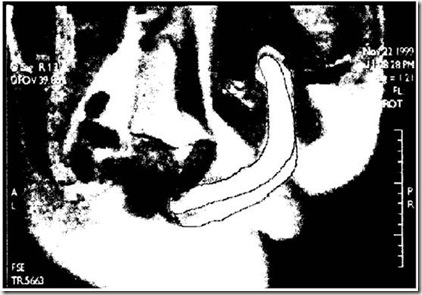

20120216002

“传教士体位”的核磁共振成像图(右边为男性。红色线条表示的是阴茎的弯曲情况。线段的长度并不代表各段阴茎的实际长度。用红色线段标记仅为方便读者观看图片内容。)

法国的研究人员使用相同的检测手段也得出了相似的结果,而且从他们获得的图片中,一眼就能看出那支“回旋镖”。